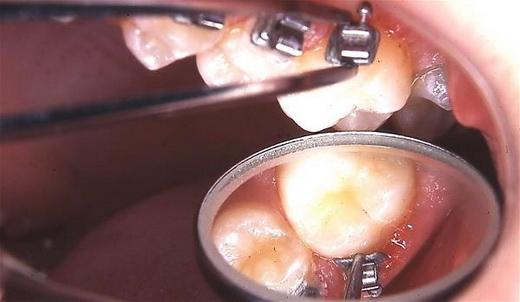

Schwierige Zahnbewegungen mit selbstligierenden Minibrackets (SPEED) & SpeedPositioner - Ganz einfach?

Dr. M. Sc. Peter Kleemann führte 1981 das Speed-Minibracketsystem in Deutschland ein und entwickelte besondere Techniken und Lösungsansätze zur Praxisreife, um die Minibrackets für verankerungsschonende komplexe Behandlungen und schwierige Zahnbewegungen einzusetzen. In der Regel kann z. B. auf den sonst notwendigen Gesichtsbogen oder die Gesichtsmaske verzichtet werden.